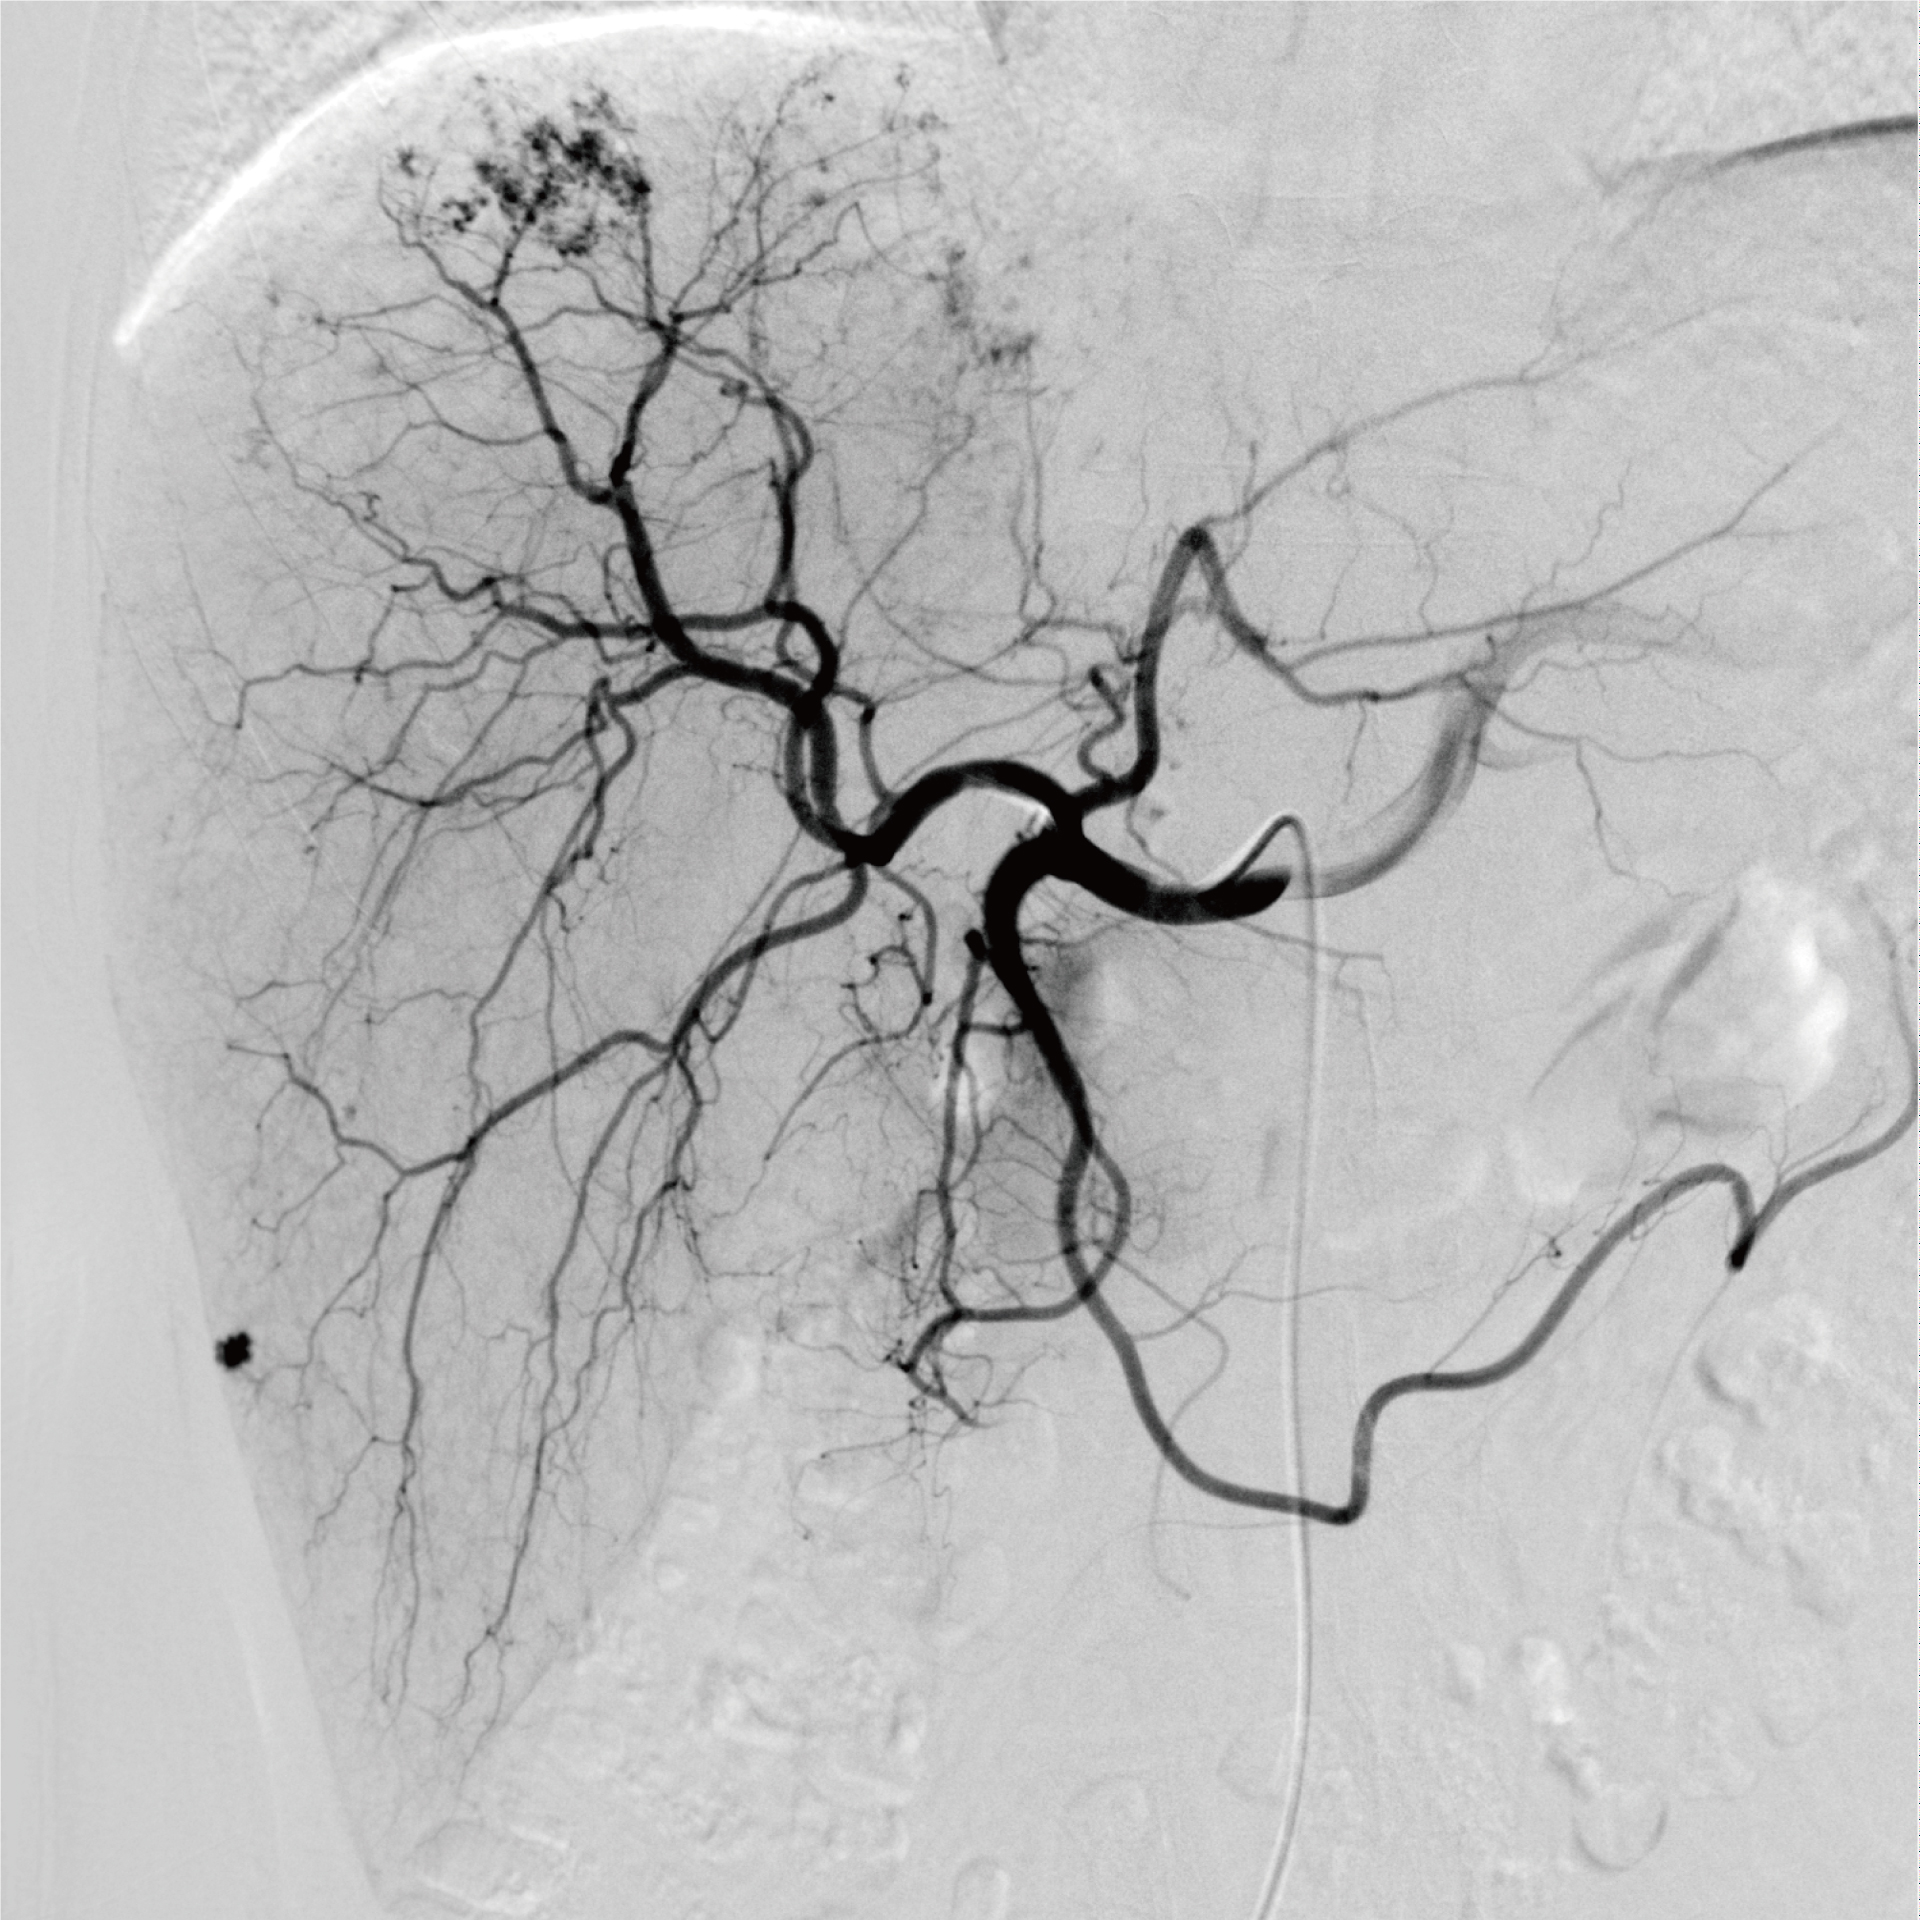

肝臟造影-唯邁醫(yī)療極光平板DSA供圖